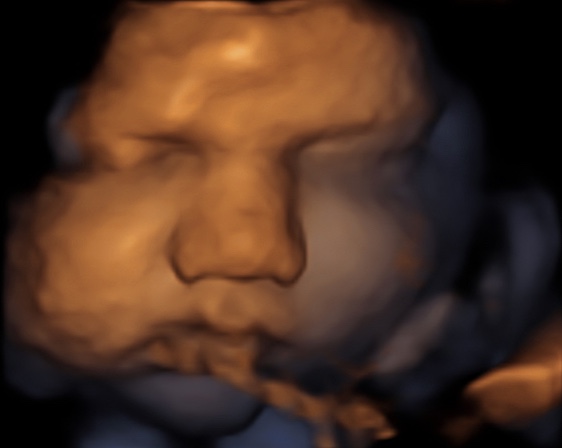

34 weken

Een echo na 34 weken.